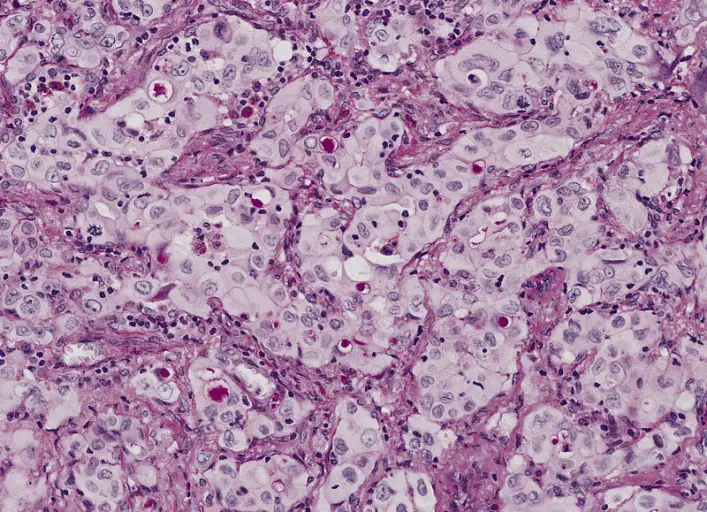

Che cos’è l’adenocarcinoma Gli adenocarcinomi sono tumori indifferenziati e maligni, le tipologie che insorgono nel contesto dell’ esofago di Barrett sono generalmente localizzati nell’esofago distale e possono invadere il cardias adiacente. ...